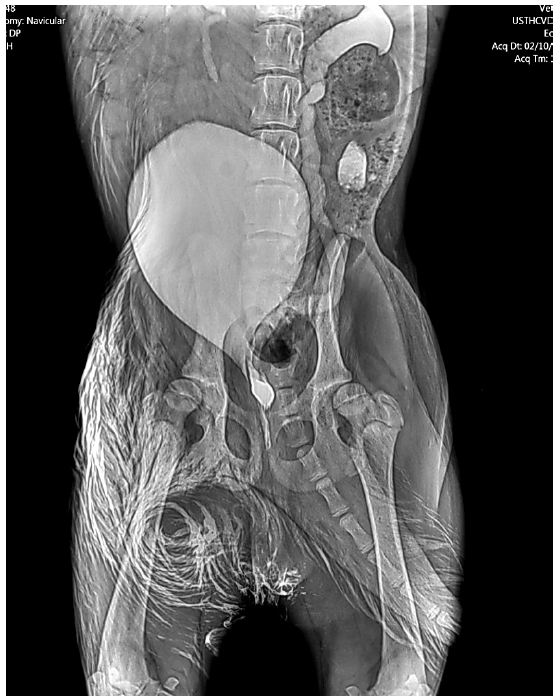

Se realizó una urografía excretora [1] y vaginourocistografía retrógrada [6], para lo cual se solicitó un periodo de 24 horas (h) de ayuno, enemas de limpieza con lactulosa (Laboratorio Mintlab, Chile) para evitar la interferencia con las imágenes radiográficas, y fluidoterapía de mantención equivalente a un paciente insuficiente renal agudo, para mantener una correcta hidratación previa al estudio. Se utilizó Omnipaque ™ (GE Health Care, Chile) Iohexol a una dosis de 1200 mg/kg diluíidos en igual volumen de solución salina, en infusión lenta. En las vistas latero-laterales se evidenció el aumento de tamaño de uno de los uréteres, y en la vista ventro-dorsal se visualizó hidronefrosis e hidrouréter con recorrido tortuoso, así como también la ectopia unilateral de tipo intramural del uréter izquierdo (FIG. 2).